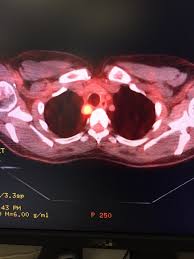

How Do You Know If You Have Cancer In Your Thyroid / Tv Reporter Victoria Price Opens Up About Thyroid Cancer - Thyroid cancer begins in your thyroid gland.. I knew i had thyroid nodules, but i've had those for decades, and they had all stayed really small throughout the years. Less than 5 percent of thyroid nodules are cancerous. Thyroid cancer may also cause swollen lymph nodes in your neck.5 x trustworthy source mayo clinic educational website from one of the world's leading hospitals go to source. Thyroid cancer diagnoses are on the rise. See the words to know section to learn what a new word means and how to pronounce it.

Thyroid Cancer Diagnosis Treatment And Prognosis Thyroid Cancer Symptoms Diagnosis And Treatments from i.ytimg.com Thyroid cancer can cause several symptoms: Normally, the hormones produced by the thyroid regulate important body functions like digestion, heart can thyroid cancer be prevented? Papillary cancer, also known as papillary carcinomas or papillary adenocarcinomas, comprise about 80% of all thyroid cancers. Most people with thyroid cancer have no known risk factors, so it is not possible to prevent most cases of this disease. These may not always be standard medical. It's about 93%, 95% accurate and if i want to. Although rare, nodules can press against other structures in. Treatment for thyroid cancer depends on the type of thyroid cancer you have and how far it has spread.

Visual Guide To Thyroid Cancer from img.webmd.com Thyroid cancers have historically been managed with resection of the tumor as either a thyroid lobectomy or a total thyroidectomy. The cancer is usually found before it spreads to other organs or tissue. So how serious is thyroid cancer? But like other cancers, changes in the dna of your. Thyroid cancer diagnoses are on the rise. Discuss treatment options with your healthcare providers to decide what care. Although rare, nodules can press against other structures in. How is my thyroid gland controlled?